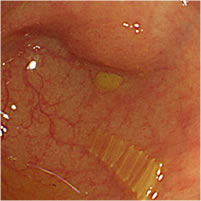

大腸ポリープ(NBI、狭帯光観察と大腸ポリープ切除)

大腸ポリープ(NBI、狭帯光拡大観察)

ポリープとは粘膜の表面に盛り上がってできるもので、病名ではなく形態を示します。ポリープには良性のものと悪性のものがあり、大腸の場合は良性と言っても悪性化することのない過形成性ポリープと、見つかった時は良性でも、そのまま切除せずに放置することで数年後にがんに変わる可能性のある大腸腺腫があります。大腸腺腫ががんに変わるリスクや時期を予測することはできません。大腸カメラ検査での早期検診、がん化する前の段階でポリープを取り除くことが大切です。